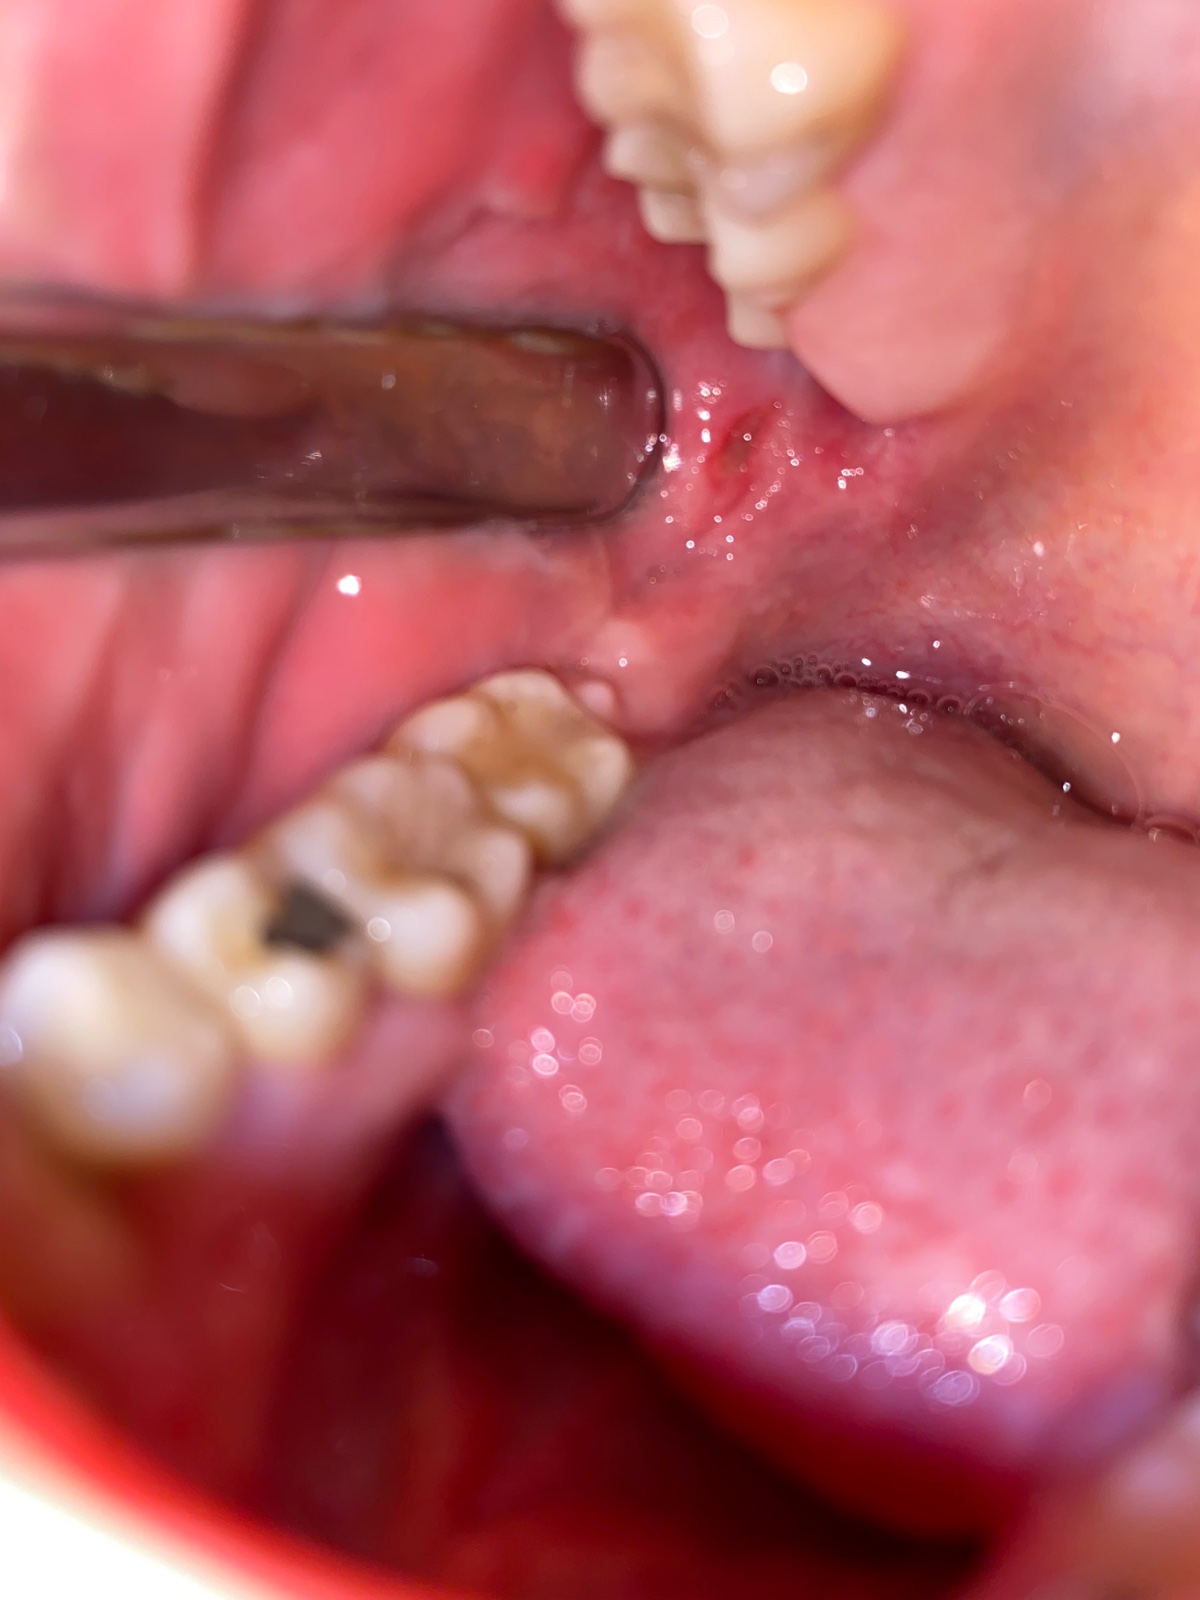

Ahojte prosím o radu o čo by mohlo ísť? Už asi 3 dni mám v ústach takúto vec a zhoršuje sa to a strašne to boli nemôžem prehĺtať jesť piť proste nič. Najskôr to začalo iba bolesťou pri prehĺtaní potom som čítala akoby mi zub rezal kozu osmičku mám vonku už niekoľko rokov no on včera som spravila takáto diera a zväčšuje sa mohla sa nejak pohnúť osmička a takto mi tam rezať líce alebo je to afta alebo moze ísť aj o niečo vážnejšie. Za všetky rady ďakujem.

To je afta. Mam takú "dieru" na jazyku a teda nič moc.